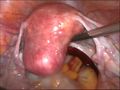

laparoscopical hysterectomy

-